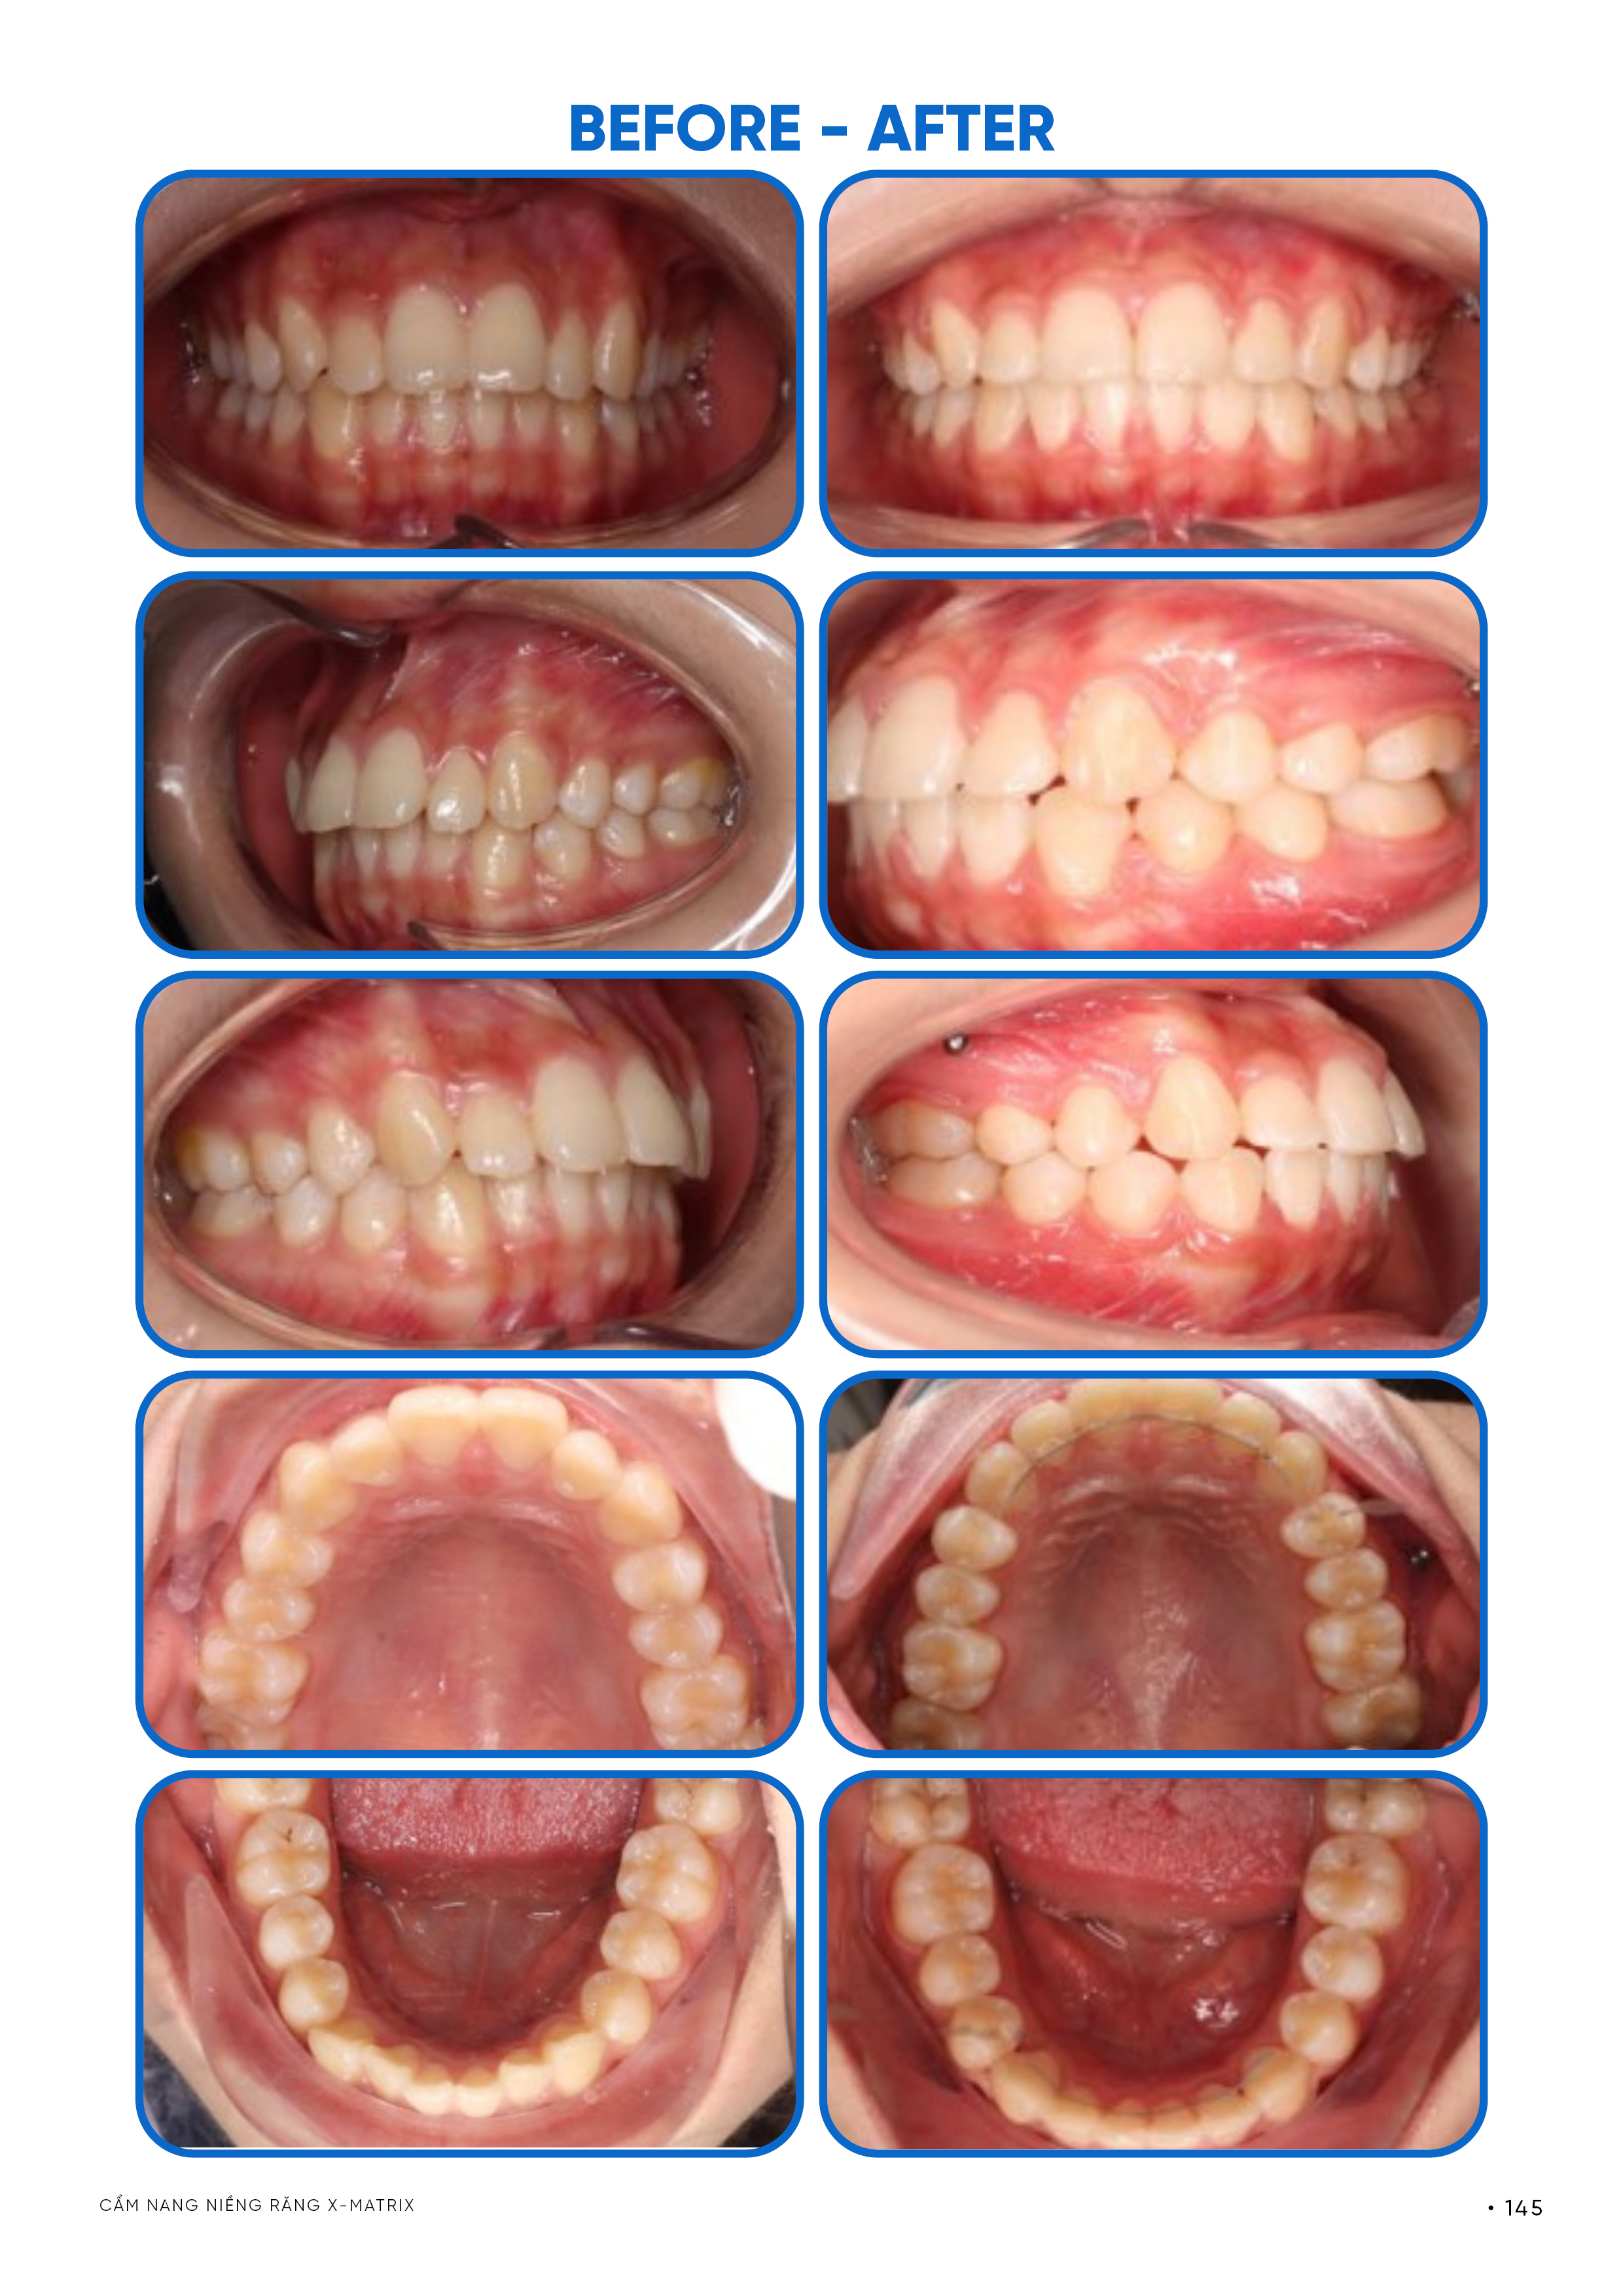

Tại Lạc Việt Intech, một ca niềng răng không được kết thúc dựa trên cảm quan “đã đẹp”, mà phải được đánh giá theo một hệ tiêu chuẩn cụ thể. Các tiêu chuẩn này nhằm kiểm định xem kết quả đạt được có đúng về sinh học, chức năng và khả năng duy trì hay chưa.

Tiêu chuẩn thẩm mỹ được xác định dựa trên sự hài hòa tổng thể khuôn mặt, trong đó vị trí răng phải phù hợp với tương quan môi – cằm và mặt nghiêng. Kết quả không chỉ được đánh giá khi cười mà còn ở trạng thái nghỉ, đảm bảo môi khép tự nhiên và biểu cảm khuôn mặt không bị thay đổi theo hướng mất cân đối.

Tiêu chuẩn chức năng yêu cầu khớp cắn đạt trạng thái ổn định, với tiếp xúc răng chính xác và phân bố lực nhai cân bằng. Không tồn tại điểm chạm sớm gây lệch hàm, và chuyển động đóng – mở hàm diễn ra tự nhiên, không có dấu hiệu bù trừ chức năng.

Tiêu chuẩn ổn định được đánh giá dựa trên vị trí răng trong vùng cân bằng lực sinh lý. Răng sau điều trị không chỉ giữ được nhờ khí cụ duy trì mà phải có khả năng tự ổn định trong môi trường lực của môi, má và lưỡi, hạn chế tối đa nguy cơ tái phát.

Tiêu chuẩn sinh học (an toàn) yêu cầu chân răng nằm hoàn toàn trong giới hạn xương ổ, không có dấu hiệu tiêu chân răng hoặc tổn thương mô nâng đỡ. Đây là tiêu chí bắt buộc và được kiểm tra bằng phim X-quang, nhằm đảm bảo rằng kết quả đạt được không đánh đổi bằng tổn thương mô.

Tiêu chuẩn kiểm soát điều trị thể hiện qua mức độ trùng khớp giữa kế hoạch và kết quả thực tế. Trong hệ thống X-Matrix, kết quả đã được mô phỏng trước, vì vậy sai lệch càng nhỏ thì mức độ kiểm soát càng cao, đồng thời phản ánh tính chính xác của toàn bộ quá trình điều trị.